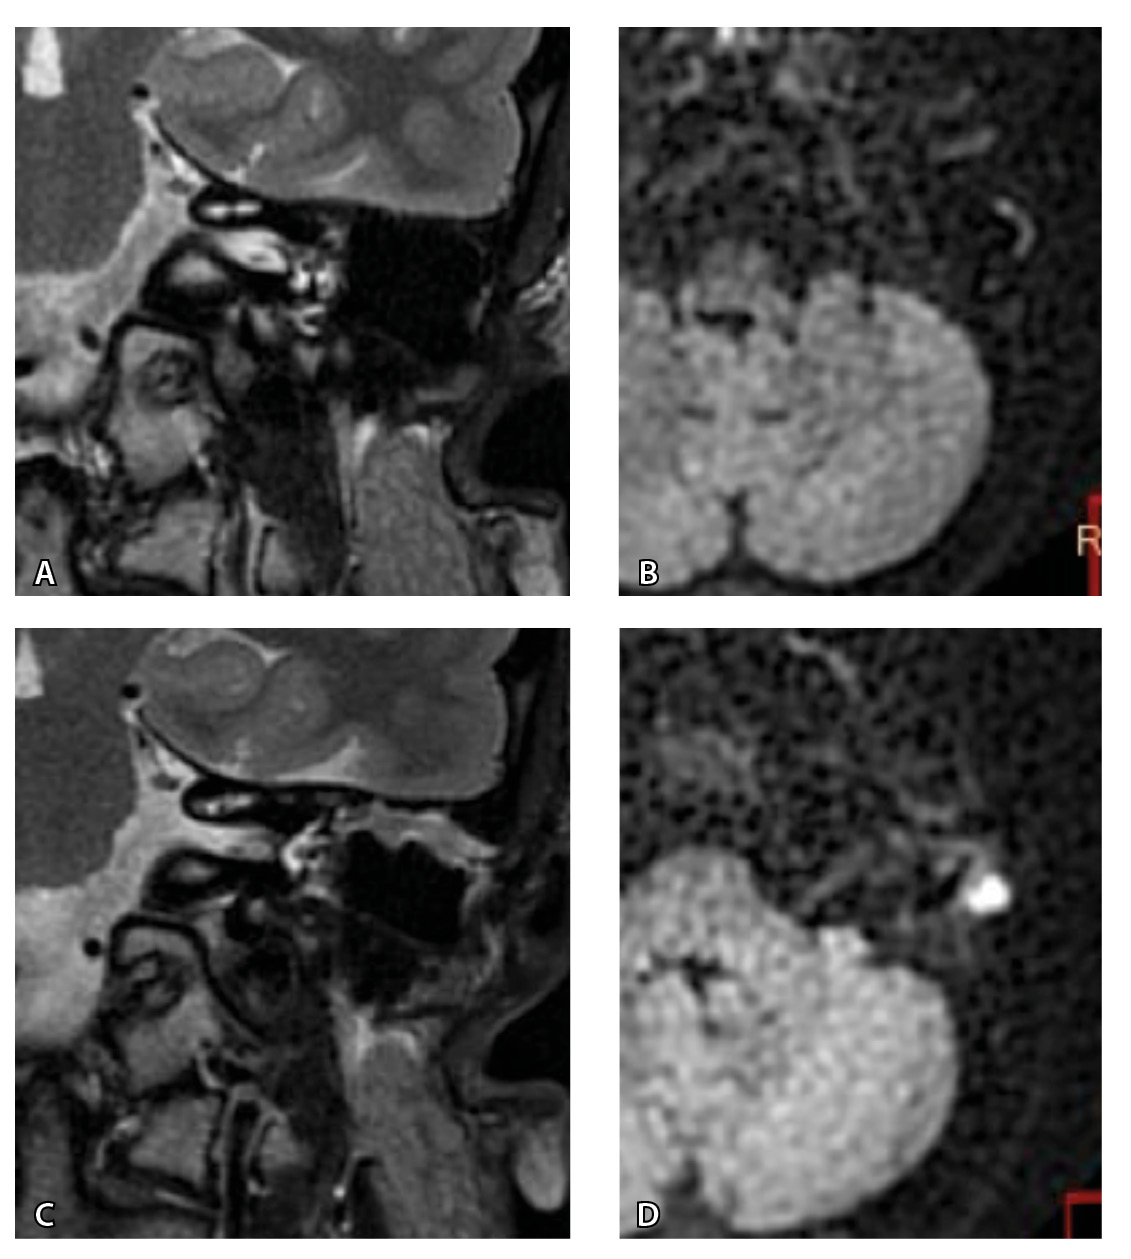

На рис. 3 и 4 показано расхождение данных КТ и МРТ.

Рис. 4. При компьютерной томографии (КТ) визуализируются признаки хронического гнойного среднего отита справа. Наблюдаются латерализация косточек среднего уха и узурация их по имедиальной поверхности на уровне эпитимпанума (тело наковальни и головка молоточка) – классические КТ-признаки холестеатомы натянутой части барабанной перепонки (А, Б). Однако по данным магнитно-резонансной томографии (В) и в последующем при оперативном лечении холестеатома не подтверждена